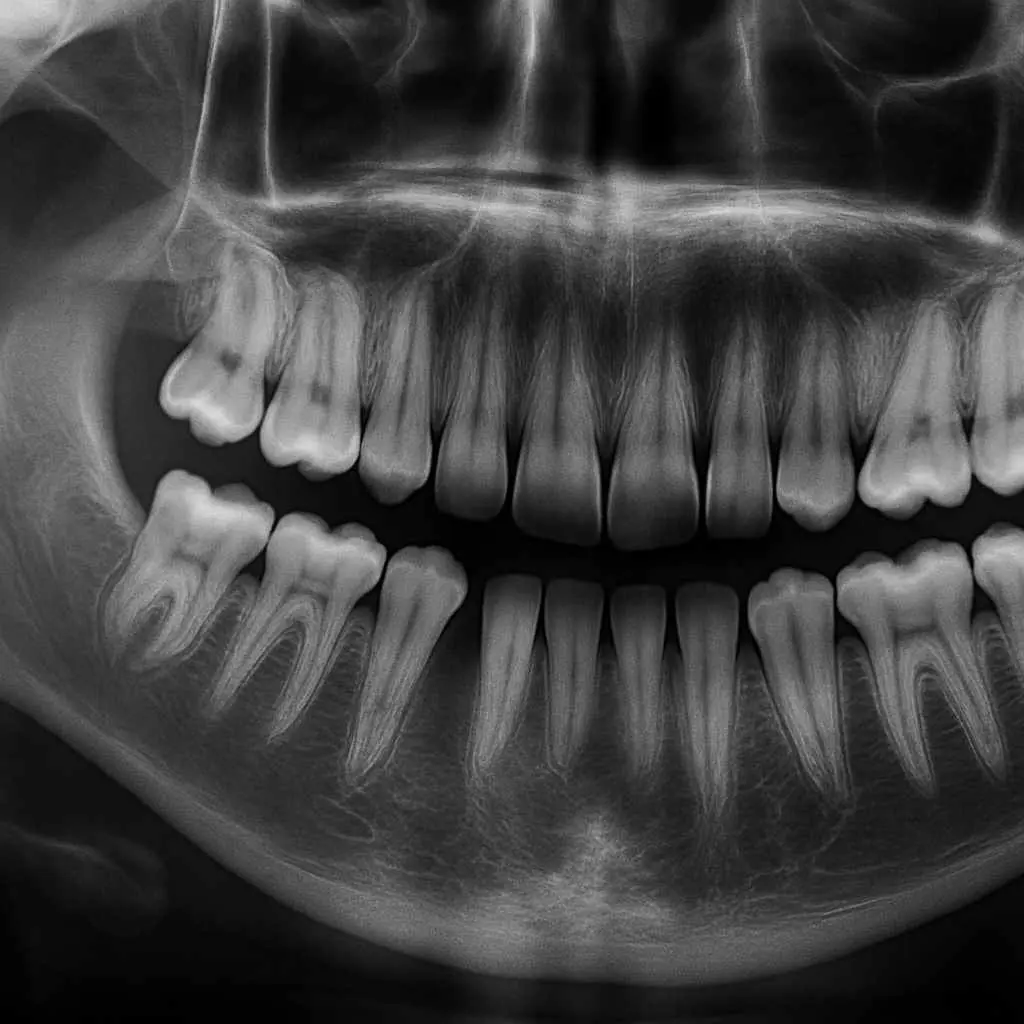

A great new trial on hemisection vs extraction to intercept missing mandibular second premolars?

Congenital absence of mandibular second premolars is relatively common. One treatment option when permanent tooth extractions are not needed as part of orthodontic treatment is to extract the deciduous molar and allow for spontaneous closure of the space. This has the advantage of promoting spontaneous space closure without orthodontic appliances.Â

An alternative treatment involves dividing the second molar and extracting the medial and distal segments at different time points. It has been suggested that this leads to better or more controlled spontaneous space closure.